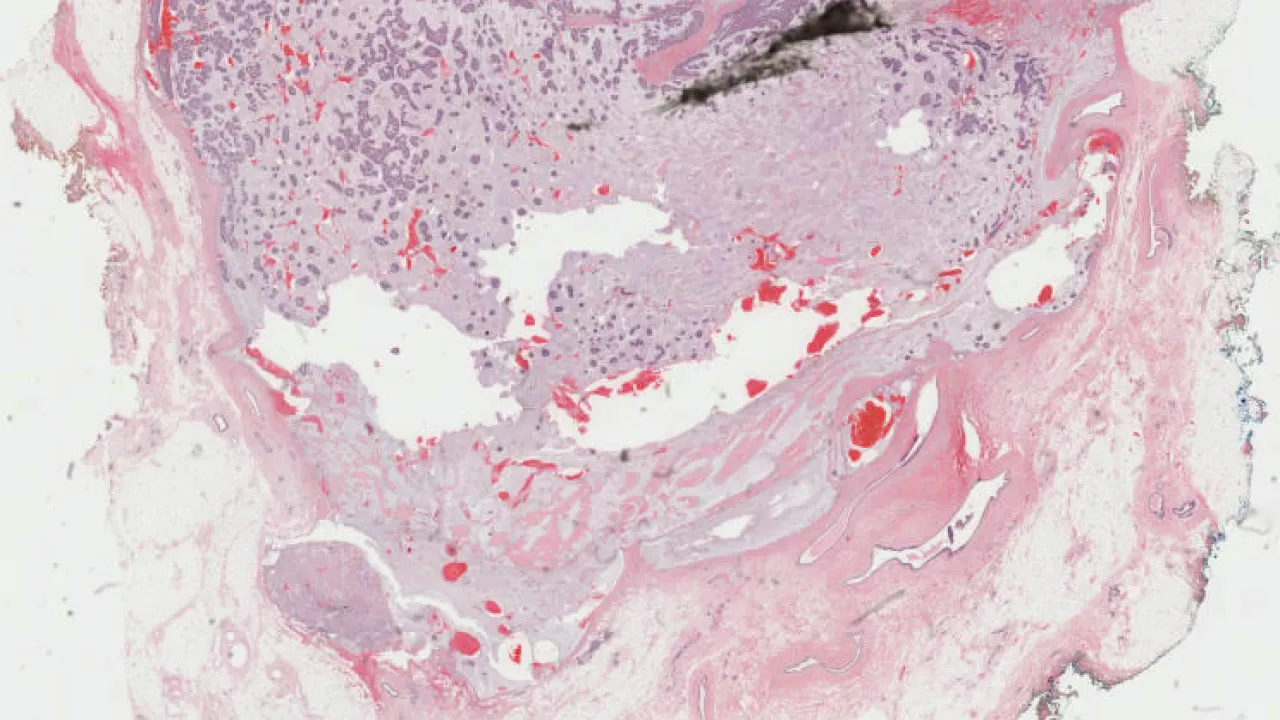

Breast, Benign phyllodes tumour